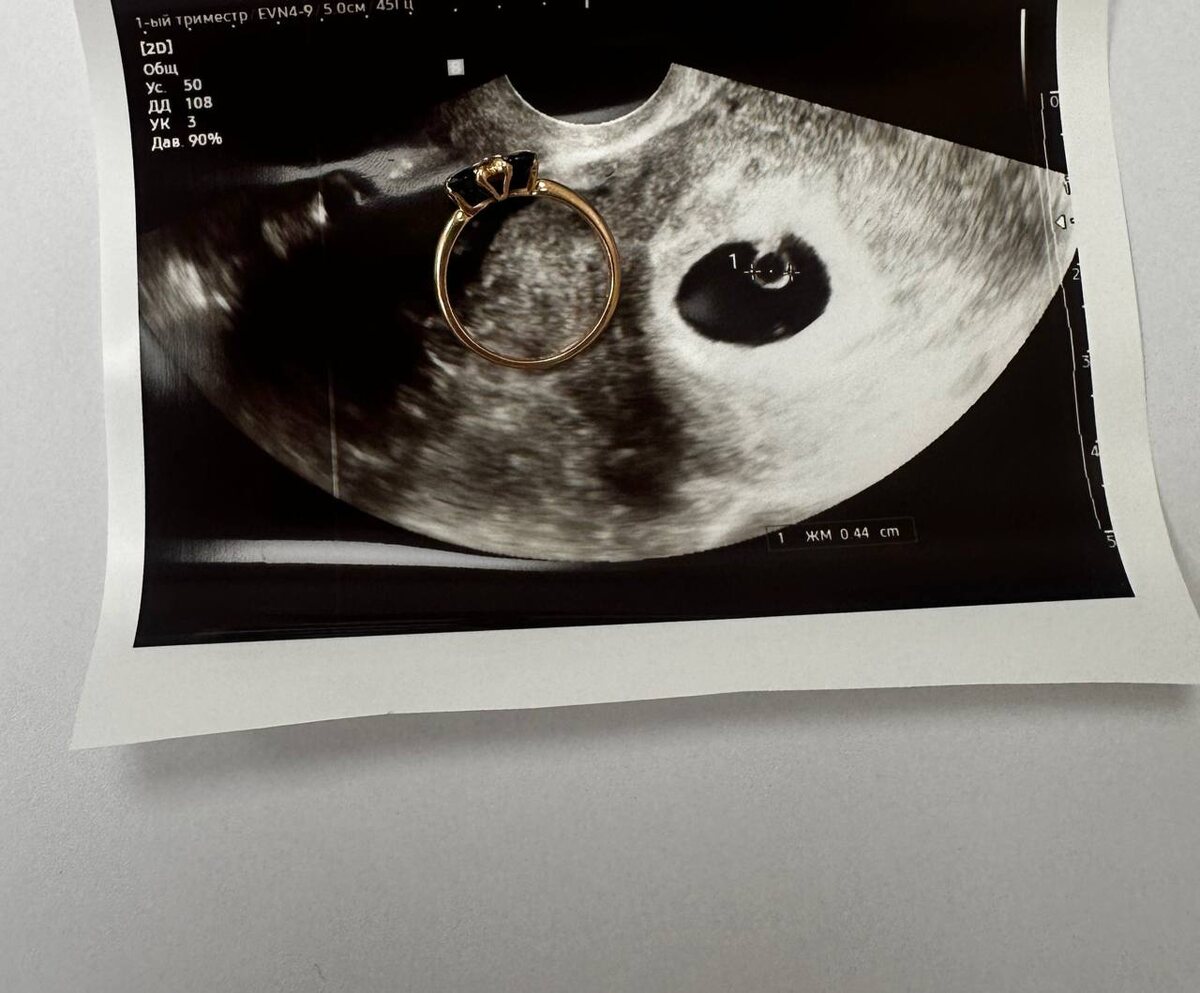

СИМПТОМ «КОЛЬЦА С БРИЛЛИАНТОМ

» Это ранний ультразвуковой признак маточной беременности. Где кольцо это желточный мешок,а бриллиант это сам маленький эмбрион 😍

СИМПТОМ «КОЛЬЦА С БРИЛЛИАНТОМ»

Это ранний ультразвуковой признак маточной беременности.

Где кольцо это желточный мешок,а бриллиант это сам маленький эмбрион 😍